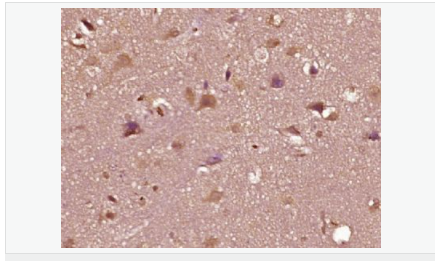

| 產(chǎn)品應(yīng)用 | WB=1:500-2000 ELISA=1:5000-10000 IHC-P=1:100-500 IHC-F=1:100-500 Flow-Cyt=1ug/Test IF=1:100-500 (石蠟切片需做抗原修復(fù)) not yet tested in other applications. optimal dilutions/concentrations should be determined by the end user. |

| 產(chǎn)品介紹 | The androgen receptor gene is more than 90 kb long and codes for a protein that has 3 major functional domains: the N-terminal domain, DNA-binding domain, and androgen-binding domain. The protein functions as a steroid-hormone activated transcription factor. Upon binding the hormone ligand, the receptor dissociates from accessory proteins, translocates into the nucleus, dimerizes, and then stimulates transcription of androgen responsive genes. This gene contains 2 polymorphic trinucleotide repeat segments that encode polyglutamine and polyglycine tracts in the N-terminal transactivation domain of its protein. Expansion of the polyglutamine tract causes spinal bulbar muscular atrophy (Kennedy disease). Mutations in this gene are also associated with complete androgen insensitivity (CAIS). Two alternatively spliced variants encoding distinct isoforms have been described. [provided by RefSeq, Jul 2008] Function: Steroid hormone receptors are ligand-activated transcription factors that regulate eukaryotic gene expression and affect cellular proliferation and differentiation in target tissues. Transcription factor activity is modulated by bound coactivator and corepressor proteins. Transcription activation is down-regulated by NR0B2. Activated, but not phosphorylated, by HIPK3 and ZIPK/DAPK3. [ENZYME REGULATION] AIM-100 (4-amino-5,6-biaryl-furo[2,3-d]pyrimidine) suppresses TNK2-mediated phosphorylation at Tyr-267. Inhibits the binding of the Tyr-267 phosphorylated form to androgen-responsive enhancers (AREs) and its transcriptional activity. Subunit: Binds DNA as a homodimer. Part of a ternary complex containing AR, EFCAB6/DJBP and PARK7. Interacts with HIPK3 and NR0B2 in the presence of androgen. The ligand binding domain interacts with KAT7/HBO1 in the presence of dihydrotestosterone. Interacts with EFCAB6/DJBP, PELP1, PQBP1, RANBP9, RBAK, SPDEF, SRA1, TGFB1I1, ZNF318 and RREB1. Interacts with ZMIZ1/ZIMP10 and ZMIZ2/ZMIP7 which both enhance its transactivation activity. Interacts with SLC30A9 and RAD54L2/ARIP4. Interacts via the ligand-binding domain with LXXLL and FXXLF motifs from NCOA1, NCOA2, NCOA3, NCOA4 and MAGEA11. The AR N-terminal poly-Gln region binds Ran resulting in enhancement of AR-mediated transactivation. Ran-binding decreases as the poly-Gln length increases. Interacts with HIP1 (via coiled coil domain). Interacts (via ligand-binding domain) with TRIM68. Interacts with TNK2. Interacts with USP26. Interacts with RNF6. Interacts (regulated by RNF6 probably through polyubiquitination) with RNF14; regulates AR transcriptional activity. Interacts with PRMT2 and TRIM24. Interacts with GNB2L1/RACK1. Interacts with RANBP10; this interaction enhances dihydrotestosterone-induced AR transcriptional activity. Interacts with PRPF6 in a hormone-independent way; this interaction enhances dihydrotestosterone-induced AR transcriptional activity. Interacts with STK4/MST1. Interacts with ZIPK/DAPK3. Interacts with LPXN. Interacts with MAK. Part of a complex containing AR, MAK and NCOA3. Subcellular Location: Nucleus. Cytoplasm. Note=Predominantly cytoplasmic in unligated form but translocates to the nucleus upon ligand-binding. Can also translocate to the nucleus in unligated form in the presence of GNB2L1. Tissue Specificity: Isoform 2 is mainly expressed in heart and skeletal muscle. Post-translational modifications: Sumoylated on Lys-386 (major) and Lys-520. Ubiquitinated. Deubiquitinated by USP26. 'Lys-6' and 'Lys-27'-linked polyubiquitination by RNF6 modulates AR transcriptional activity and specificity. Phosphorylated in prostate cancer cells in response to several growth factors including EGF. Phosphorylation is induced by c-Src kinase (CSK). Tyr-534 is one of the major phosphorylation sites and an increase in phosphorylation and Src kinase activity is associated with prostate cancer progression. Phosphorylation by TNK2 enhances the DNA-binding and transcriptional activity and may be responsible for androgen-independent progression of prostate cancer. Phosphorylation at Ser-81 by CDK9 regulates AR promoter selectivity and cell growth. Phosphorylation by PAK6 leads to AR-mediated transcription inhibition. Palmitoylated by ZDHHC7 and ZDHHC21. Palmitoylation is required for plasma membrane targeting and for rapid intracellular signaling via ERK and AKT kinases and cAMP generation. DISEASE: Defects in AR are the cause of androgen insensitivity syndrome (AIS) [MIM:300068]; previously known as testicular feminization syndrome (TFM). AIS is an X-linked recessive form of pseudohermaphroditism due end-organ resistance to androgen. Affected males have female external genitalia, female breast development, blind vagina, absent uterus and female adnexa, and abdominal or inguinal testes, despite a normal 46,XY karyotype. Defects in AR are the cause of spinal and bulbar muscular atrophy X-linked type 1 (SMAX1) [MIM:313200]; also known as Kennedy disease. SMAX1 is an X-linked recessive form of spinal muscular atrophy. Spinal muscular atrophy refers to a group of neuromuscular disorders characterized by degeneration of the anterior horn cells of the spinal cord, leading to symmetrical muscle weakness and atrophy. SMAX1 occurs only in men. Age at onset is usually in the third to fifth decade of life, but earlier involvement has been reported. It is characterized by slowly progressive limb and bulbar muscle weakness with fasciculations, muscle atrophy, and gynecomastia. The disorder is clinically similar to classic forms of autosomal spinal muscular atrophy. Note=Caused by trinucleotide CAG repeat expansion. In SMAX1 patients the number of Gln ranges from 38 to 62. Longer expansions result in earlier onset and more severe clinical manifestations of the disease. Note=Defects in AR may play a role in metastatic prostate cancer. The mutated receptor stimulates prostate growth and metastases development despite of androgen ablation. This treatment can reduce primary and metastatic lesions probably by inducing apoptosis of tumor cells when they express the wild-type receptor. Defects in AR are the cause of androgen insensitivity syndrome partial (PAIS) [MIM:312300]; also known as Reifenstein syndrome. PAIS is characterized by hypospadias, hypogonadism, gynecomastia, genital ambiguity, normal XY karyotype, and a pedigree pattern consistent with X-linked recessive inheritance. Some patients present azoospermia or severe oligospermia without other clinical manifestations. Similarity: Belongs to the nuclear hormone receptor family. NR3 subfamily. Contains 1 nuclear receptor DNA-binding domain. SWISS: P10275 Gene ID: 367 Database links: Entrez Gene: 367 Human Entrez Gene: 11835 Mouse Omim: 313700 Human SwissProt: P10275 Human SwissProt: P19091 Mouse Unigene: 496240 Human Unigene: 39005 Mouse Unigene: 394224 Mouse Unigene: 439657 Mouse Unigene: 9813 Rat Important Note: This product as supplied is intended for research use only, not for use in human, therapeutic or diagnostic applications. AR是一個由917個氨基酸組成的蛋白質(zhì),位于雄激素靶組織細(xì)胞中或細(xì)胞表面上的特異分子部位或結(jié)構(gòu)。 AR在前列腺癌中起著重要的作用,研究表明AR的表達(dá)與組織分型形成一定的相關(guān)性 ,AR在高分化的腫瘤中表達(dá)較多,而在低分化的腫瘤中表達(dá)較少。用于前列腺癌的檢測,指導(dǎo)臨床治療,目前可用于乳腺癌、食道癌等各項(xiàng)腫瘤的研究。 |